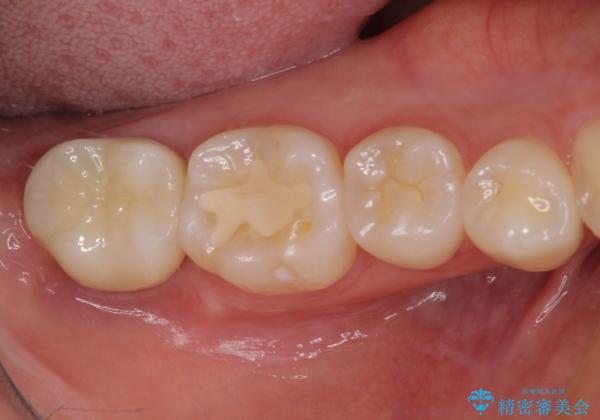

クラウンがすぐに外れてしまう 歯冠長延長術を用いた補綴治療

- 奥歯のかぶせものが頻繁に脱離することを気にされて来院された患者様です。

歯の高さが低く、かぶせものを安定して維持させることができないため、歯冠長延長術により歯の高さを増大させた上で、オールセラミッククラウンにて補綴することとしました。

クラウンが外れている期間も長く、虫歯が進行していたため、根管治療も行うこととしました。

歯の高さが増したことで、かぶせものが外れにくくなったことはもちろん、今まで無理と言われていたセラミッククラウンも装着でき、さらには歯間部の清掃性も向上したため、患者様には大変満足していただけました。